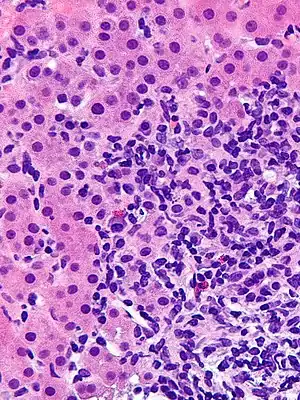

| Micrograph showing a lymphoplasmacytic interface hepatitis—the characteristic finding of autoimmune hepatitis. Liver biopsy. H&E stain. | |

Histological features supportive of a diagnosis of autoimmune hepatitis include:[10]

- A mixed inflammatory infiltrate centered on the portal tract

- The inflammatory infiltrate may breach the interface between the portal tract and liver parenchyma: so-called interface hepatitis

- The most numerous cell in the infiltrate is the CD4-positive T cell.

- Plasma cells may be present within the infiltrate. These are predominantly IgG-secreting.

- Eosinophils may be present within the infiltrate.

- Emperipolesis, where there is penetration of one cell through another, within the inflammatory infiltrate

- Varying degrees of necrosis of periportal hepatocytes.

- In more severe cases, necrosis may become confluent with necrotic bridges forming between central veins.

- Hepatocyte apoptosis manifest as acidophils or apoptotic bodies.

- Rosettes of regenerating hepatocytes.

- Any degree of fibrosis from none to advanced cirrhosis

- Biliary inflammation without destruction of biliary epithelial cells in a minority of cases.